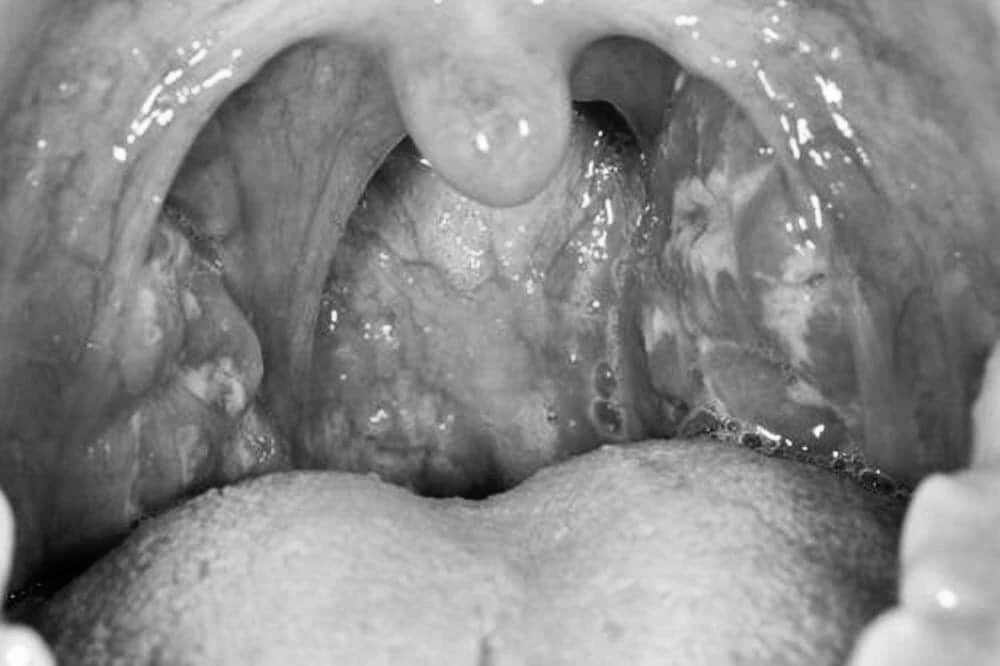

Các dấu hiệu viêm họng do liên cầu khuẩn tan huyết nhóm A thường thấy là đau họng dữ dội, không ho, sốt cao, khó nuốt, amidan sưng to, đỏ và có mủ; hạch cổ sưng to, đau...

Tình trạng cổ họng bị viêm. Ảnh: BSCC